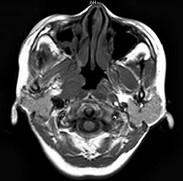

问题 女,34岁。右侧听力下降,耳鸣2个月。MRI平扫及增强扫描如图示,最可能的诊断是()

选项 A.鼻咽癌 B.脑膜瘤 C.神经源性肿瘤 D.动脉瘤 E.未见异常

答案 A